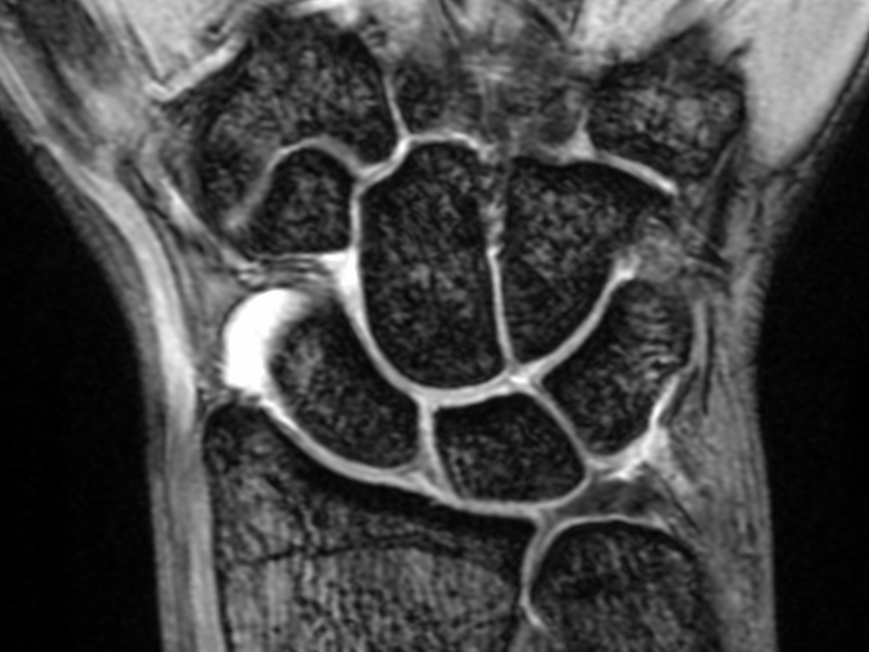

CT / MRI

◯ CTならびにMRI検査は当ビル1階のセントラルCIクリニックに依頼し、放射線科医による専門的な診断を得ています。